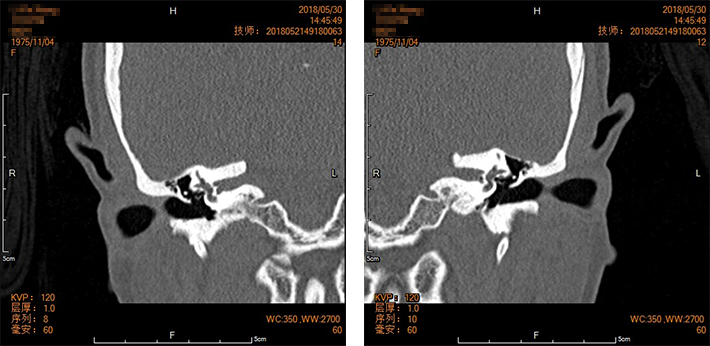

声导抗:双耳鼓室A型曲线。乳突CT:双侧镫骨脚附着处前庭窗、圆窗密度增高、增厚。双侧鼓膜完整,鼓室内清朗,听小骨链完整。考虑双侧耳硬化症(窗前型)。住院后选择先行左耳手术。

术前检查:

CT影像检查